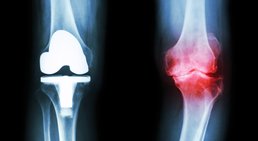

Mein fachärztlicher Schwerpunkt liegt in der Behandlung des Kniegelenks. Durch die internationale Ausbildung an einer Knieklinik, aktive Mitgliedschaft in zahlreichen wissenschaftlichen Fachgesellschaften sowie langjährige Erfahrung führe ich auch komplexe Knieoperationen (u.a. Meniskustransplantation) und Kombinationseingriffe in höchster Fallzahl in Wien durch.